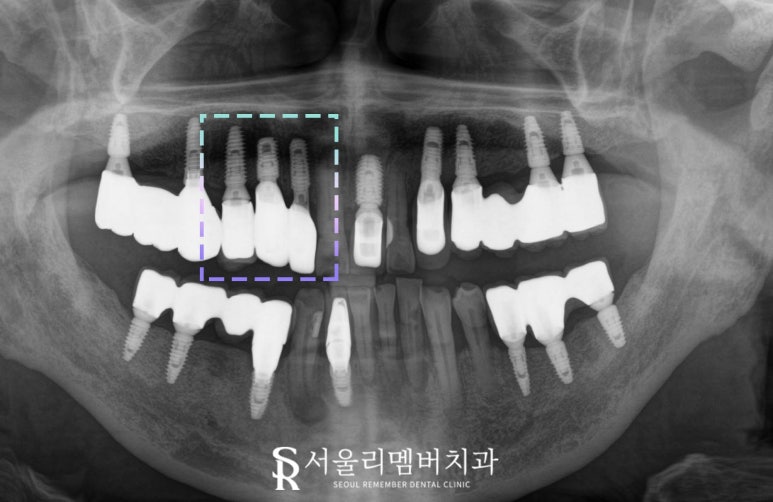

오늘 서울대입구역 치과 에서 설명드리는 케이스는

손상된 측절치와 송곳니에는

발치 후 임플란트가 필요합니다.

측절치는 파절이 심해

크라운을 씌우기에도 어려움이 있으며,

송곳니는 깊은 우식이 치근까지 진행되어

신경치료만으로는

장기적인 예후가 좋지 않았습니다.

또한 첫 번째 작은 어금니는

기존 임플란트 위에 새로운 크라운 보철을 제작하여

외관을 회복해 주는 것이 좋겠습니다.

결과적으로 세 개의 전치부 모두

기능과 외관이 성공적으로 복원되었고,

환자는 더 이상 통증 없이

정상적인 저작 기능을 회복하셨을 것입니다.

2025.01.07

또한 임플란트 보철만 새로 제작함으로써

비용은 최소화하고

나에게 맞는 맞춤형 크라운으로

심미성도 지킬 수 있답니다.